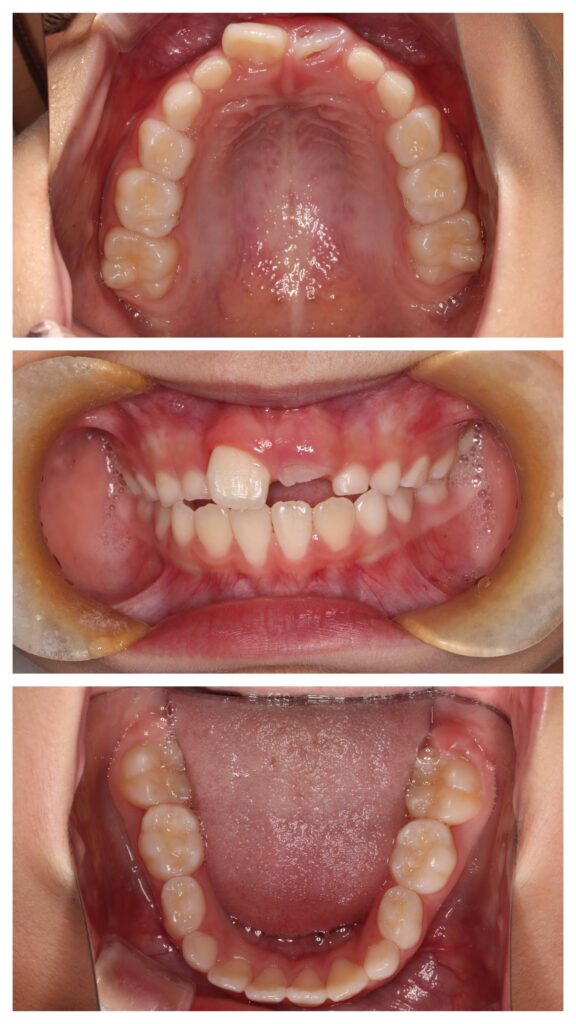

症例紹介①(顎顔面矯正)

今回の症例では、

成長期に上顎の拡大装置を使用。

BEFORE

歯列が狭く、前歯のスペース不足が認められました。

AFTER

歯列はU字型へ拡大。

永久歯が並ぶ余裕のあるアーチへ改善しました。